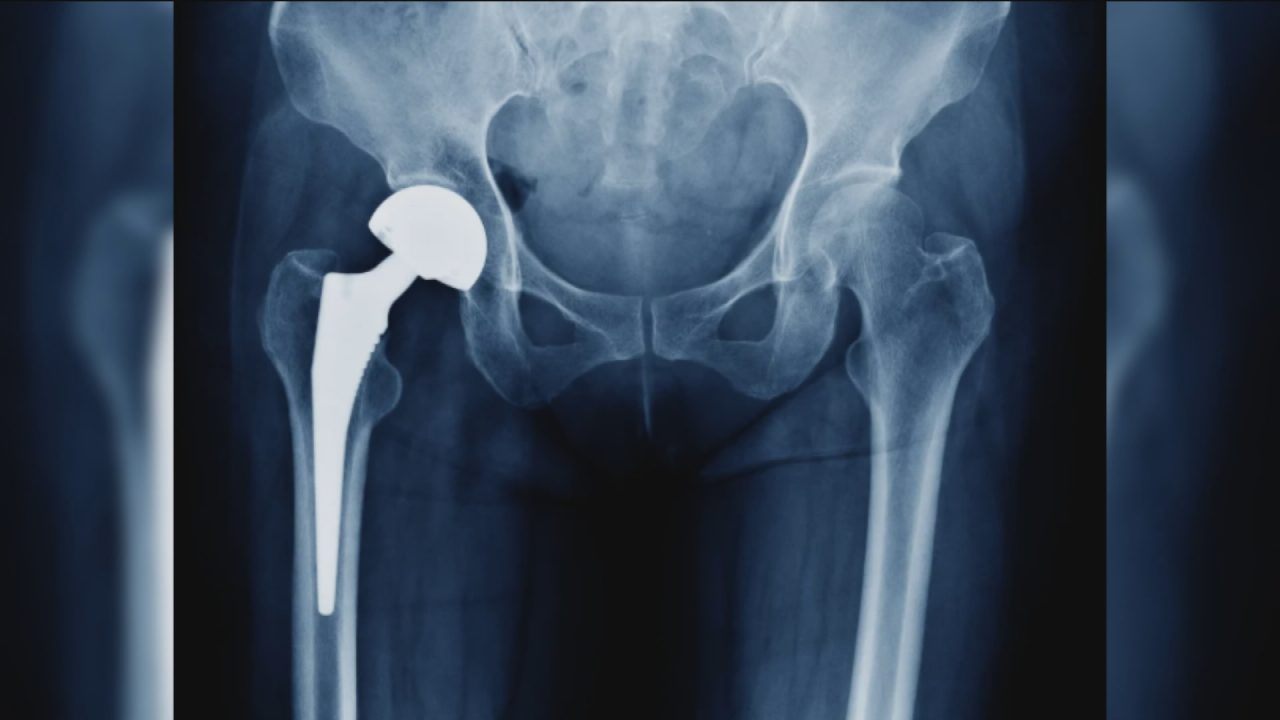

An Edinburgh woman who says she was left “crippled” by a metal hip implant is demanding answers from its manufacturer, claiming the prosthetic almost “poisoned her to death.”

Lilias Watters says metal from the prosthetic leeched into her body causing fatigue and debilitating pain.

Around 120,000 hip replacement surgeries are carried out every year in the UK – the vast majority are a success, with life changing results.